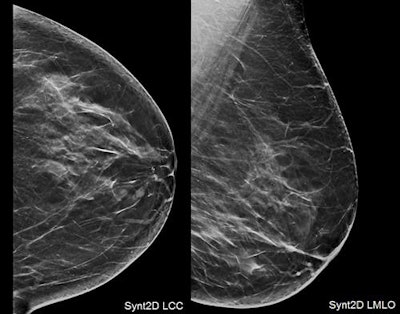

Top: Small, ill-defined mass identified scrolling through DBT slices. Bottom: DBT spot-compression views emphasized the tiny spiculations, increasing the level of suspicion (the lesion was classified BI-RADS 5 category). All images courtesy of Dr. Daniela Bernardi."Our results indicate that DBT screening improves screening-detection metrics," Bernardi told attendees at ECR 2018. "However, further research needs to assess health benefits."